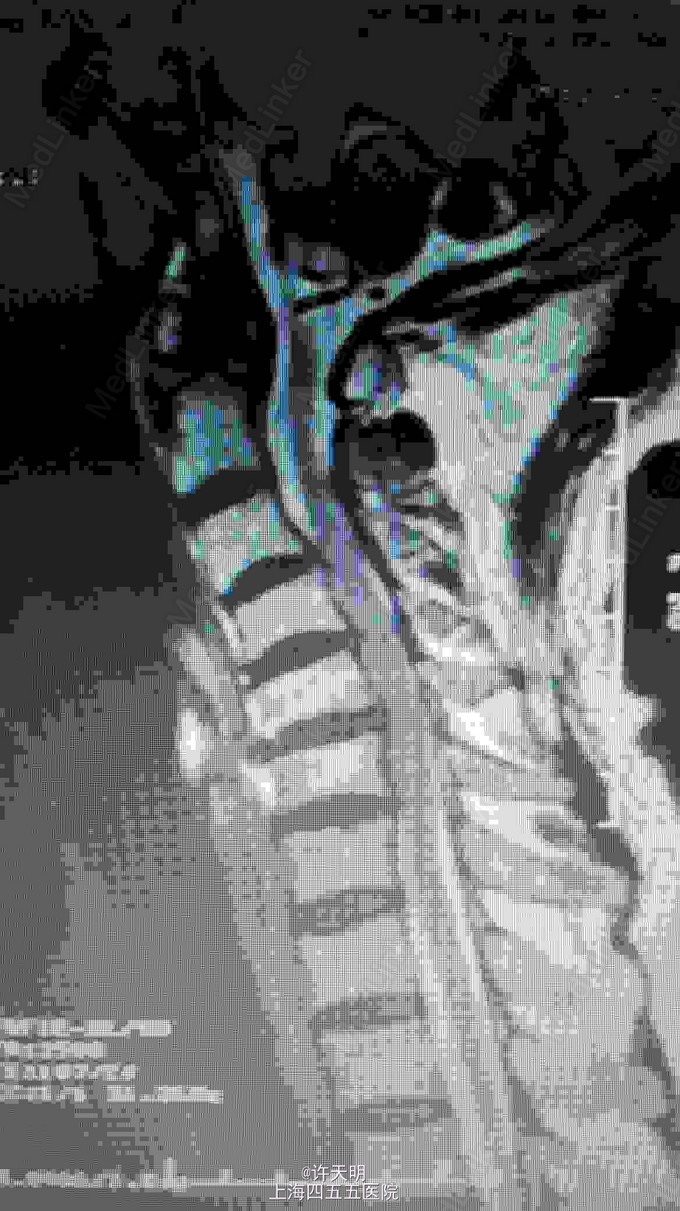

颈椎后路钉棒固定手术

脊髓型颈椎病 颈椎病

老年男性,行走不稳半年。

双下肢肌张力增高,双下肢肌力下降,病理反射阳性。

脊髓型颈椎病,行颈后路减压固定手术。

由于患者颈椎曲度差,不建议行颈椎管成型手术,建议行后路钉棒固定,有一定矫形作用。